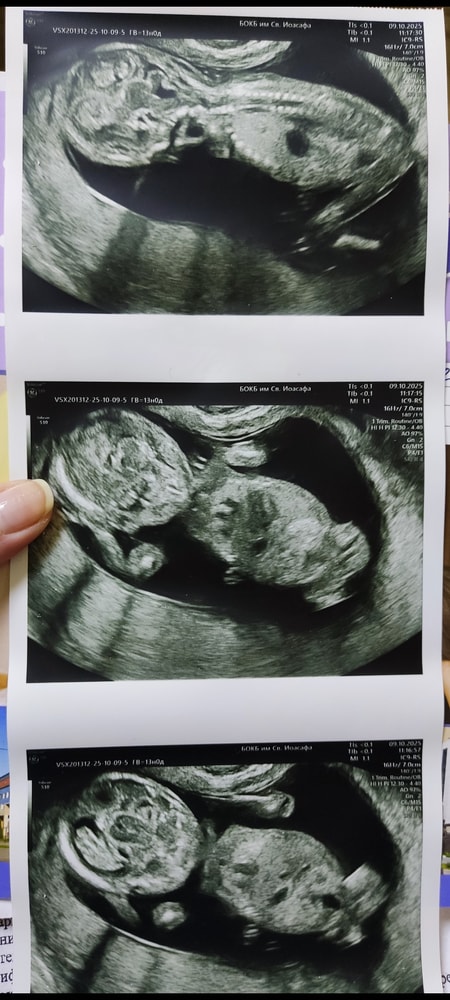

УЗИ первого скрининга ❤️💙 Девочки, видите пол?

Ну и самое интересное 🙂 пол. Кто-нибудь что-нибудь видит??? На УЗИ сказала, что лежит малыш отвергнутым, приходить в 16 недель, чтоб наверняка. Но там уже нипт будет.

А любопытство то разбирает)